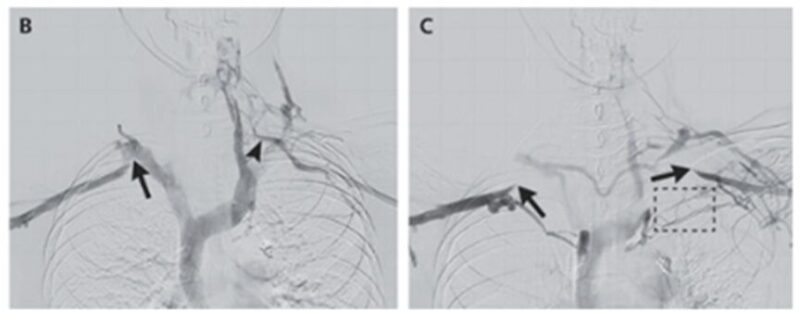

腕が下がっていると、正常な鎖骨下静脈の血流であったが(B)腕を上げて造影すると両側の鎖骨下静脈を通る血流は右も左も血流が遮断される様子が確認された(C)。

側副血管が小さい分、左からの血液排出が遅く、これが左側の症状の原因となっていると考えられた。